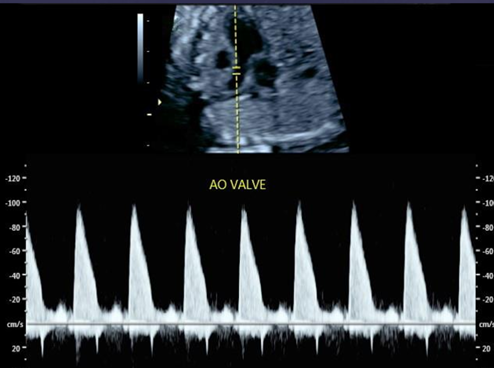

Fetal echocardiography parameter ultrasound image

Fetal Echocardiography * (2019)

Article | Image Library